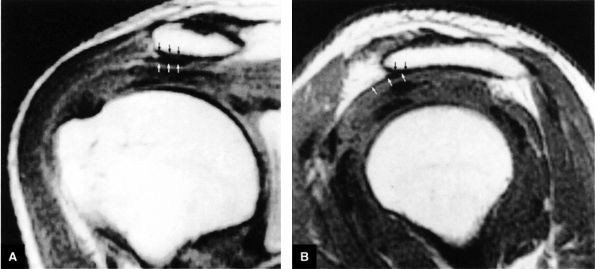

FIGURE 8.2 ● Rotator cuff tendon on coronal FS PD FSE (A) and T2 FSE (B) images using an eight-channel phased-array coil.